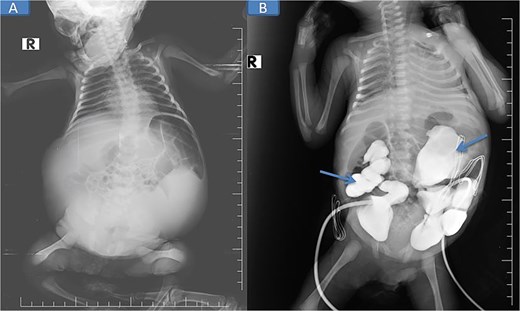

Pre-nephrostomy drainage abdominal distention (A) and post-nephrostomy (B).

Abdominal and scrotal ultrasonography demonstrated multilocular cystic hydronephrosis with thinning of renal parenchyma, extending into the pelvis, and absence of testes within the scrotum. Both testes were located intra-abdominally between bowel loops (left 7 × 4.5 mm, right 6 × 5.5 mm) (Figs 2 and 3). Abdominal X-ray after percutaneous nephrostomy with contrast revealed pooling in both kidneys without ureteric passage, suggesting bilateral ureteropelvic junction obstruction (UPJO) (Fig. 4).

Pre-op abdominal X-ray (A) and post-operative percutaneous nephrostomy procedure with contrast injection through the nephrostomy (B).

The patient was stabilized with CPAP oxygen, intravenous antibiotics (ampicillin, cefotaxime, metronidazole), and supportive care. Following preoperative evaluation and parental consent, bilateral nephrostomy was performed, yielding significant urine drainage. Postoperatively, renal function improved with normalization of creatinine and urea, and by Day 5 post-nephrostomy, values had returned to normal (urea 13 mg/dl [reference: 10–45] and creatinine 0.48 mg/dl [reference: 0.35–1.10]), accompanied by a reduction in abdominal distention.